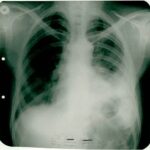

1992 yılında malign lenfoma teşhisi konulan 60 yaşındaki kadın hasta, immünomodülatör tedavi ile 6 ayda tam iyileşme sağladı. 10 yıllık takip sürecinde hastalık tamamen kontrol altındaydı ve hasta normal yaşamına döndü.

1992: 60 yaşındaki kadın hasta sol göğüs ağrısı ve öksürük şikâyetiyle başvurdu.

Plevral biyopsi yapıldı ve teşhis konuldu.

Biyopsi Sonucu: "Malign lenfoma"

Çok düşkün haldeydi. 4 mg immünomodülatör aşı sonrası ateşi 38.2°C'ye yükseldi.

Röntgende belirgin düzelme görüldü. Tedaviye devam edildi.

Tümörün tamamen kaybolduğu görüldü.

Şikâyeti kalmamıştı ve immünomodülatör tedaviyi bırakması önerildi.